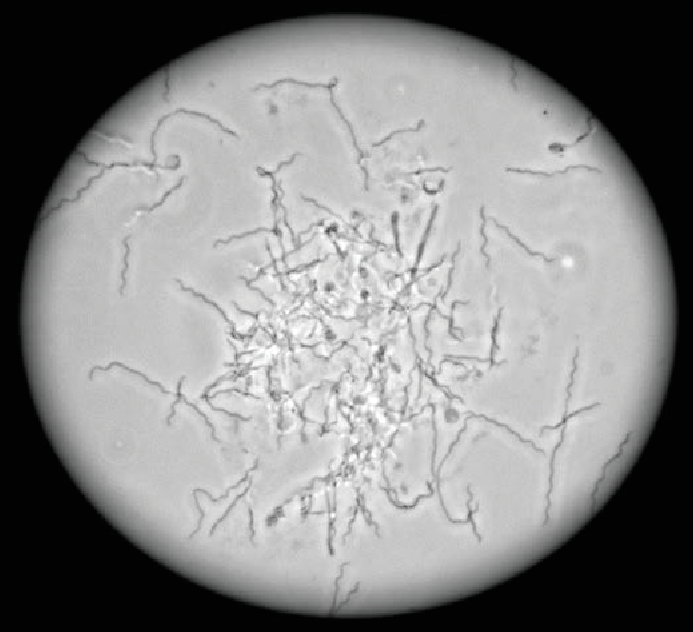

A dermatitis digitalis okát mind klasszikus mikrobiológiai, mind molekuláris biológiai módszerekkel tanulmányozták. Ezek a vizsgálatok feltárták, hogy a Treponema fajok a leggyakrabban előforduló mikroorganizmusok az ujjak közötti bőr felületén vagy annak mélyebb rétegeiben. A treponémák nem csak a szarvasmarhák számára kórokozók, mivel egyes fajok az emberek esetén szifiliszt és ínybetegséget okozhatnak. A treponémák nagyon vékony (tízszer vékonyabbak az emberi hajnál), spirál alakú (spirocheták), mozgékony anaerob baktériumok, amelyek stressz hatására cisztákat alkotnak (“spórák”). Ezek a baktériumok nagyon lassan növekedő és nagyon érzékeny szervezetek. Laboratóriumi körülmények között is csak 7 nap után történik látható növekedés. Az optimális növekedés emellett csak szűk tartományban érhető el a pH, a hőmérséklet, a tápanyagszükséglet és az oxigén koncentráció vonatkozásában. Ezek a körülmények azonban mind megfelelőek a trágyában és trágyalében, ahol a treponémák szaporodnak. Így a trágya és a trágyalé a treponémák által okozott csülökfertőzés egyik fő forrása.

Treponema spp. Mikroszkópos felvétel (40X)